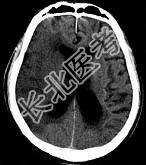

- 单项选择题女,75岁, 于昨天突发左侧肢体无力,嘴角歪斜, 言语表达不清,CT如图, 最可能的诊断是 ( )

A、右侧颞顶枕叶梗死

B、星形胶质瘤

C、脑脓肿

D、少突胶质细胞瘤

E、脑囊肿